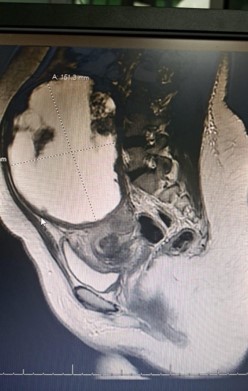

MRI of the pelvis with contrast reported bilateral ovarian dermoid cysts, with the largest measuring approximately 67×64 mm, containing fat and calcification components consistent with mature cystic teratoma. The uterus was described as unremarkable.

Figure 1: Sagittal pelvic MRI showing a large mass arising from the uterine fundus.

Figure 3: MRI sagittal section showing a large heterogeneous pelvic–abdominal mass initially interpreted as an ovarian lesion.